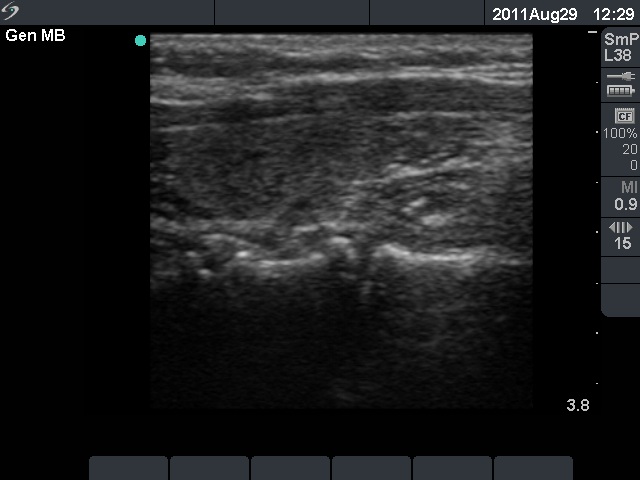

Follow-up examination 3 years later (second row of images):

Ultrasonography: The thyroid was unchanged. The lesions in the dorsal part of the right lobe increased in size and a small hypoechogenic area appeared in the ventral part of the left lobe.